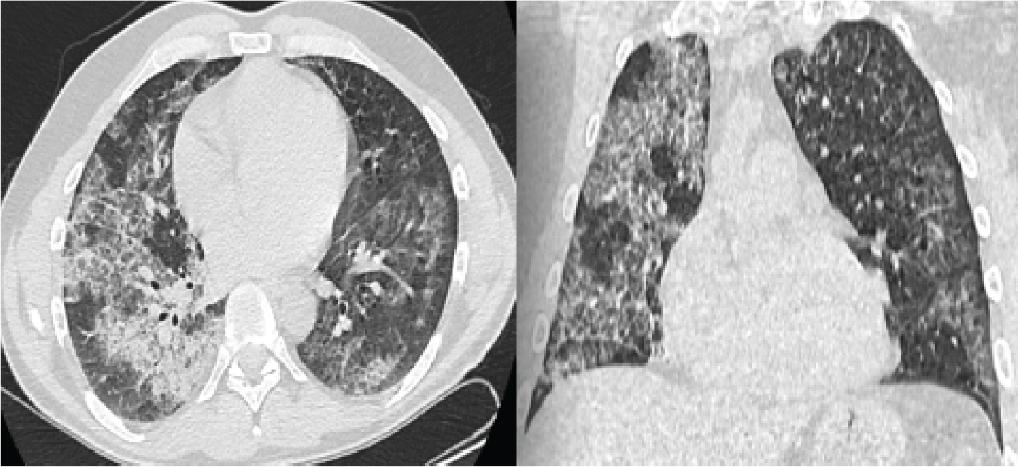

Thus, it is decided to perform therapeutic WLL using a high-frequency vibration vest, which is used for intrapulmonary mobilisation of the lavage fluid under selective intubation. Initially, the left lung is lavaged by the instillation of 17 L of physiological saline prewarmed to 37°C (Figure 4). After 30 days, the right lung is lavaged by instillation of 20 L of physiological saline prewarmed to 37°C (Figure 5), with recovery of 16.8 L and 19.8 L of characteristic milky fluid, which, as the lavage proceeds, becomes clear, with subsequent aspiration of the remaining amount bronchoscopically. The primary complications of WLL included fever (18%), hypoxaemia (14%), wheezing (6%), pneumonia (5%), pleurisy (3.1%) and pneumothorax (0.8%) (5). Fortunately, this case proceeded without intra- or postprocedural adverse events. After performing the first WLL of the left lung, although the patient’s condition improved considerably, clinically by maintaining oxygen saturations above 95% spontaneously and significant improvement of symptoms, which was also supported by the partial resolution of the initial imaging changes in the left lung (Figure 6), however, when performing the functional respiratory explorations after the left WLL, it was interesting that both spirometric parameters and Diffusing Capacity of the Lungs for Carbon Monoxide (DLCO) decreased (DLCOc = 41%, KCOc = 70%). After performing the two total lung lavages, the patient is counselled to quit smoking, advised to avoid chemicals, sawdust, synthetic fertilisers and insecticides at work, with an evaluation of changing the workplace, as well as influenza and pneumococcal vaccination and is recalled every 3 months for pulmonology re-evaluation. At 3 months post-procedure, the patient presents for followup. From the clinical point of view, we observed a significant improvement: no dyspnoea, no cough, SpO2= 99% spontaneously. Normal colour of the integuments and mucosae, lung objective, stetacustic vesicular murmur present bilaterally, without overadded rallies. From the functionally respiratory point of view, spirometry showed significantly improved bronchodilation (FVC = 115%–113%, FEV1 = 95%– 102%, FEV1/FVC = 07–0.74, FEF25–75 = 73%–77%), oscillometry within normal limits, and the gas transfer factor through the pulmonary alveolar–capillary membrane also markedly improved (DLCOc = 83% of predicted, KCOc = 94% of predicted). In addition, imaging results suggest quasicomplete remission of previous pulmonary changes (Figure 7). However, although the current clinical picture is significantly improved, contrary to medical recommendations, the patient continues to smoke and to be exposed to a toxic environment at work, a possible trigger of this pathology; thus, the long-term evolution could be jeopardised.

Computer tomography performed 4 weeks after left WLL. WLL, whole lung lavage.

Computer tomography performed 3 months after both WLL. WLL, whole lung lavage.